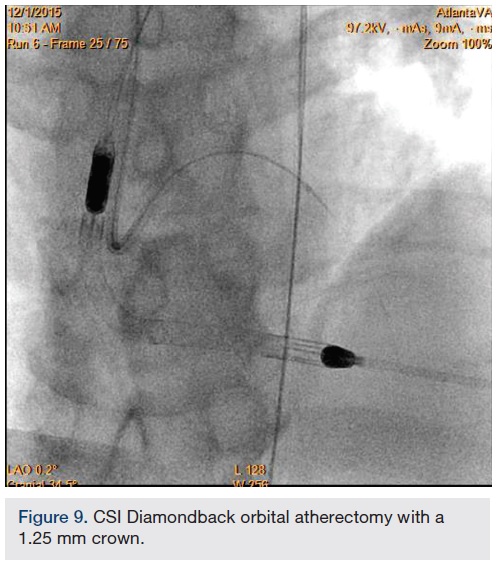

Following successful completion of the peripheral phase, it was felt that a 4-week period was necessary for the iliac stent to heal somewhat (especially since we planned to place a 14 French Cook sheath through it). We then moved on to the coronary phase of this procedure. Bilateral groins and the right wrist were prepared and draped in the usual sterile fashion. Using micropuncture technique with fluoroscopic verification of needle entry into the left CFA at the upper quadrant of the femoral head, a 6 French sheath was placed in the left CFA. The existing left femoral arterial sheath was removed, and the arteriotomy was pre-closed with a single Perclose device (Abbott Vascular). The arteriotomy was then serially dilated with 10, 12 and 14 French dilators, and a 14 French, 30 cm Cook sheath was placed successfully in the left common femoral artery. Following therapeutic anticoagulation with intravenous heparin, a regular J-wire and a 6 French pigtail catheter were used to cross the aortic valve, and the catheter was used to exchange the J wire for the 0.018-inch Platinum Plus wire (Boston Scientific). The Impella CP (3.5) percutaneous left ventricular assist device (LVAD) (Abiomed) was inserted into the left ventricle over the Platinum Plus wire (Figure 8). The Impella was then activated and good flows were verified. Right radial artery access was obtained and a PB 3.0 7.5 French sheathless guide system (Asahi Intecc) was used to engage the left main coronary artery. The LAD was wired uneventfully using a Runthrough wire (Terumo) via a 1.25 x 6 mm over-the-wire (OTW) Sprinter balloon (Medtronic). This was then exchanged for a Viper wire (CSI). Orbital atherectomy of the proximal LAD lesion was performed with excellent results (80,000 rpm x 4 passes, 120,000 rpm x 2 passes) (Figure 9). The LAD wire was then exchanged for a Runthrough wire and the left circumflex (LCX) was wired with a BMW wire. Following plaque modification with orbital atherectomy, predilation of LAD was performed with 3.0 x 20 mm Chocolate Balloon (QT Vascular Ltd) (15 atmospheres x 60 seconds and 15 atmospheres x 30 seconds) (Figure 10) with an excellent result and no dissection (Figure 11). A 3.5 x 38 mm Promus stent (Boston Scientific) (14 atmospheres x 30 seconds) was placed from the left main into the proximal LAD lesion ensuring adequate coverage. The jailed LCX wire was recovered and re-placed in the LCX through the struts of the newly placed LM-LAD stent (Figure 12). Predilation of the LCX ostium was performed with a 2.5 x 8 mm Glider balloon (QT Vascular Ltd) (14 atmospheres x 25 seconds). The mid LAD was stented (ensuring overlap with proximal stent) with 3.0 x 16 mm Promus stent (16 atmospheres x 25 seconds). A final kissing balloon inflation of the LAD/LCX with an NC Sprinter 2.5 x15 mm balloon (Medtronic) into the LCX and a NC Sprinter 3.5 x12 mm balloon into the LAD was performed, with up to 16 atmospheres x 20 seconds on both (Figure 13). Final IVUS of the LM and LAD stent revealed excellent results and the LCX ostium looked excellent as well (Figures 14-16).

In our experience, there are significant synergies to be exploited between the CSI Diamondback atherectomy device and the Chocolate balloon (QT Vascular Ltd). The orbital atherectomy device works by shaving or sanding calcified areas of the artery and may sometimes leave calcified spicules in the vessel that can be optimally modified further with adjunctive Chocolate balloon angioplasty, thus enabling excellent stent expansion and apposition, allowing for decreased restenosis and thrombosis. The Chocolate balloon consists of a mounted nitinol constraining structure specifically designed for uniform, controlled inflation and rapid deflation, resulting in atraumatic dilatation without the need for cutting or scoring. Because of its novel design, it is able to enable focused force angioplasty from its “pillows” while allowing plaque channeling through its “grooves”.